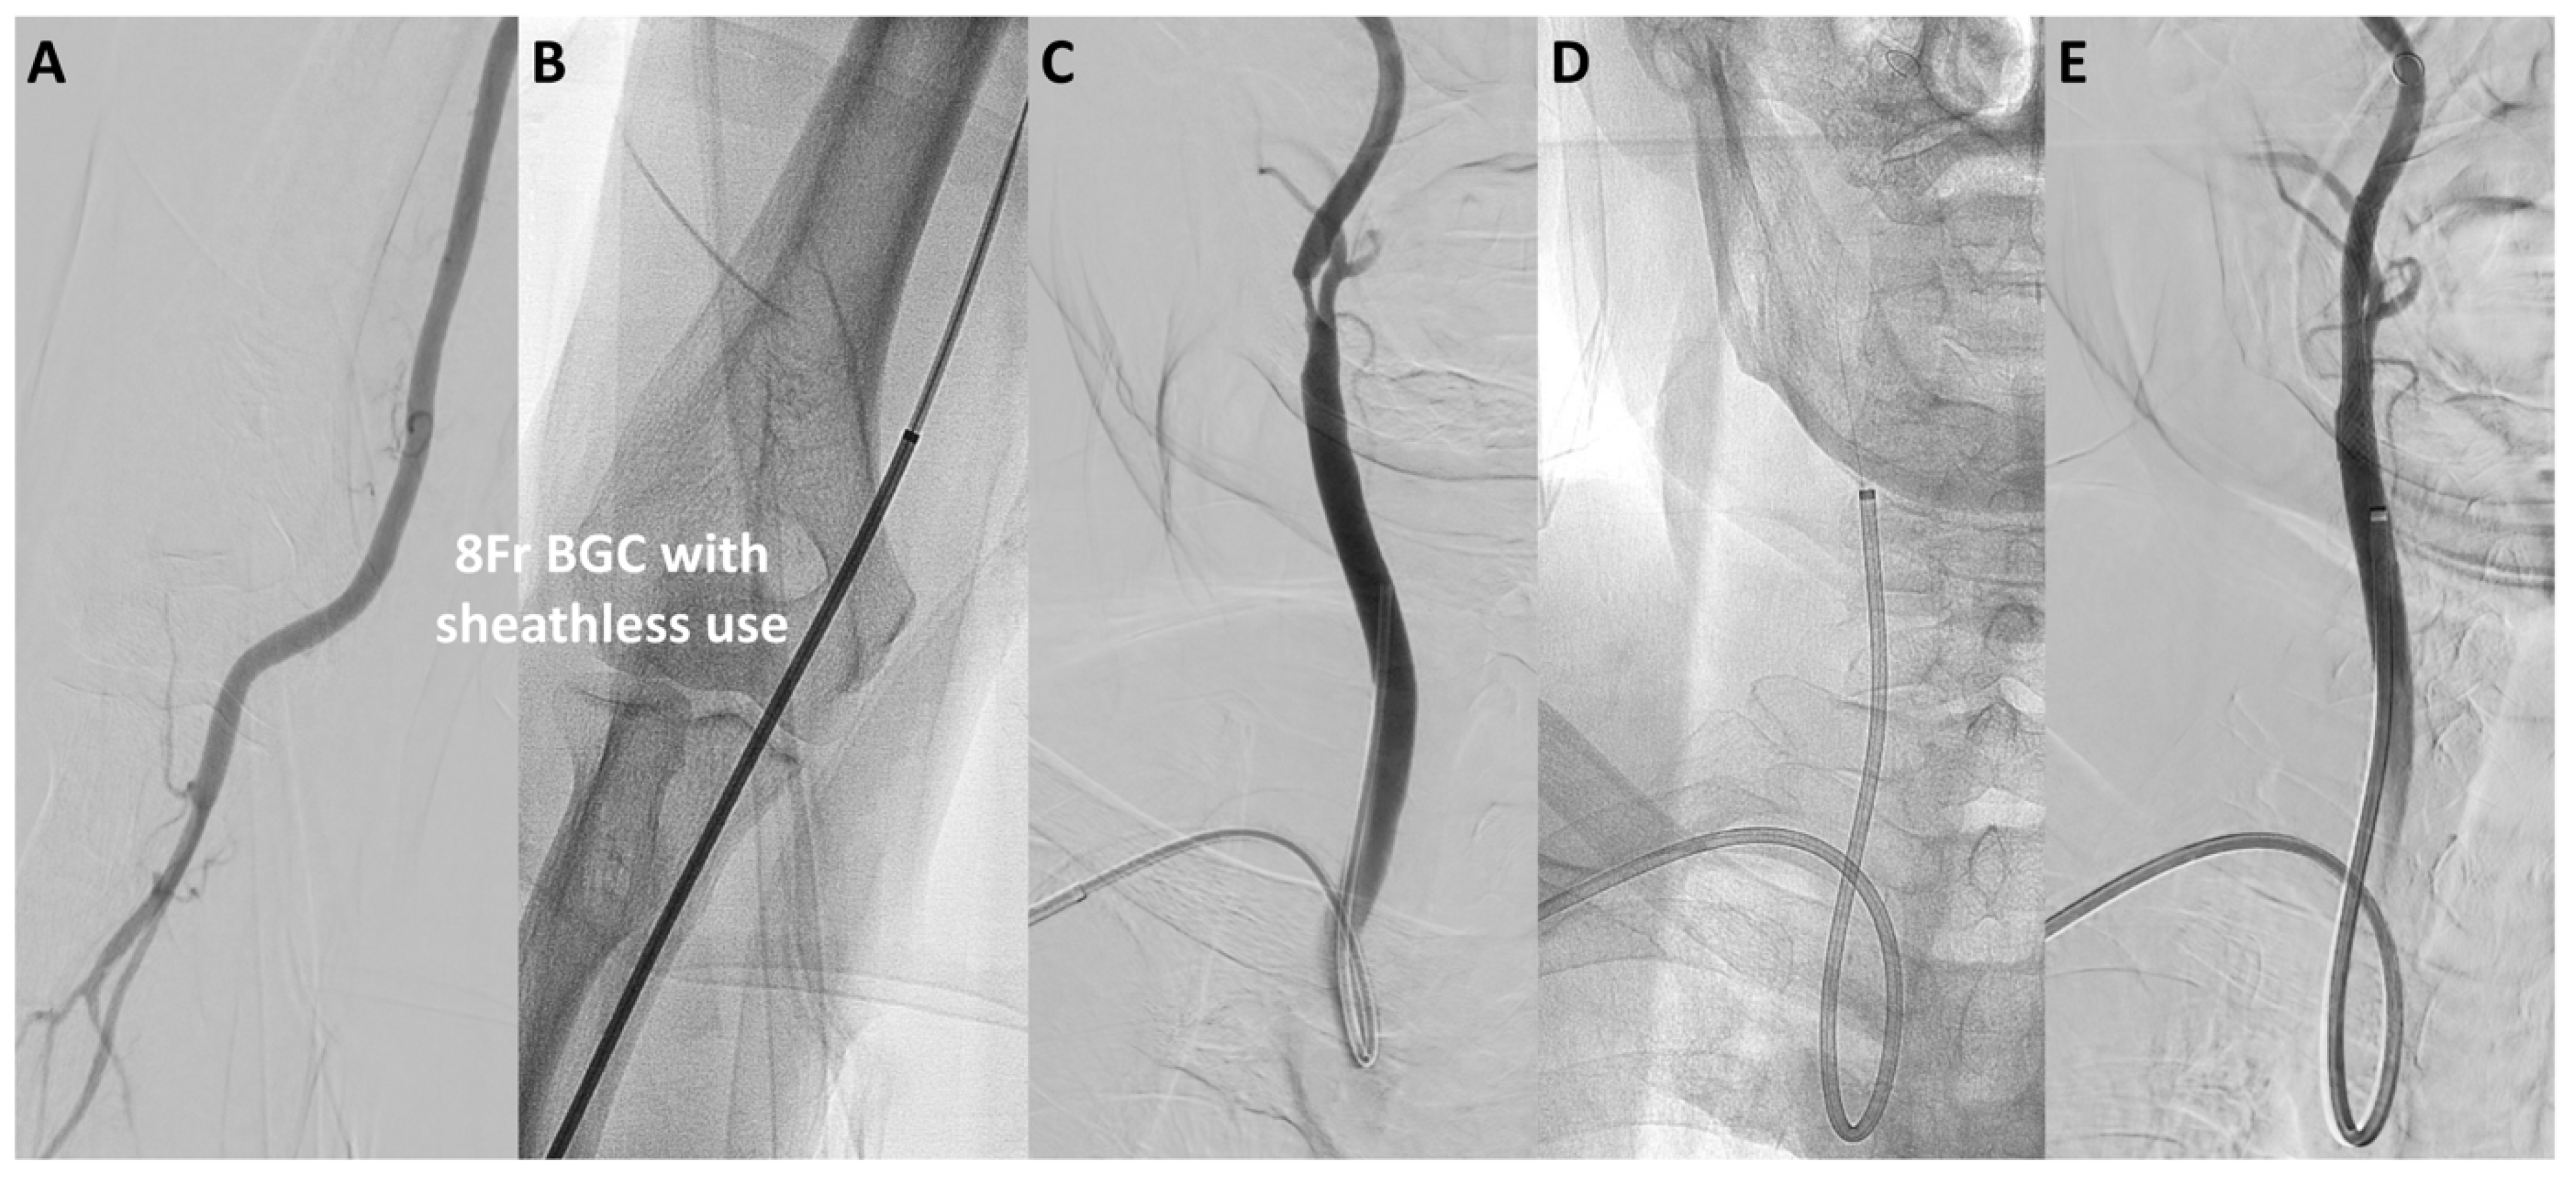

The median puncture size was reduced from 3.1 mm in the TFA-first period to 2.7 mm in the TRA-first period (p < 0.01; Figure 2B). Specifically, in the TFA-first period, the most commonly used devices were the 9Fr sheath BGC (40%) and the 6Fr guide sheath (GS) (48%). In the TRA-first period, however, the sheathless 8Fr BGC was widely used, accounting for 70% of cases, with minimal use of larger devices (p < 0.01). The widespread adoption of the sheathless 8Fr BGC during the TRA-first period was primarily due to its advantages in managing unstable plaque and providing enhanced support during device navigation. Representative cases of TRA CAS using the sheathless 8Fr BGC are illustrated in Figure 3 and Figure 4. Figure 3 shows a favorable anatomy case with smooth BGC navigation, while Figure 4 demonstrates a challenging anatomy case where BGC use was desired due to unstable plaque; however, balloon anchoring in the external carotid artery (ECA) was required to guide the BGC into position.

Figure 4. Representative case of TRA CAS in challenging approach anatomy. A representative case of TRA CAS using a sheathless 8Fr BGC in challenging approach anatomy. Aortography shows a steep angle between the brachiocephalic artery and the left common carotid artery (CCA), suggesting potential difficulty in guiding a catheter to the left CCA using TRA or TBA (A). Due to the presence of unstable plaque, a sheathless 8Fr BGC was chosen to reduce distal embolization risk. (B) illustrates the selection of the left CCA using a Simmons-type inner catheter. In (C,D), a distal protection balloon is inflated in the external carotid artery (ECA) to serve as an anchor, facilitating navigation of the guiding catheter over the sharp curve to the target site (arrow: the ECA balloon). In (E,F), during CAS, the distal protection balloon is inflated in the internal carotid artery (ICA), and the 8Fr BGC balloon is inflated to achieve flow stasis and stabilize stent delivery (double arrows: the 8Fr BGC balloon). Abbreviations: CAS, carotid artery stenting; CCA, common carotid artery; ECA, external carotid artery; ICA, internal carotid artery; BGC, balloon guide catheter; TRA, transradial access.